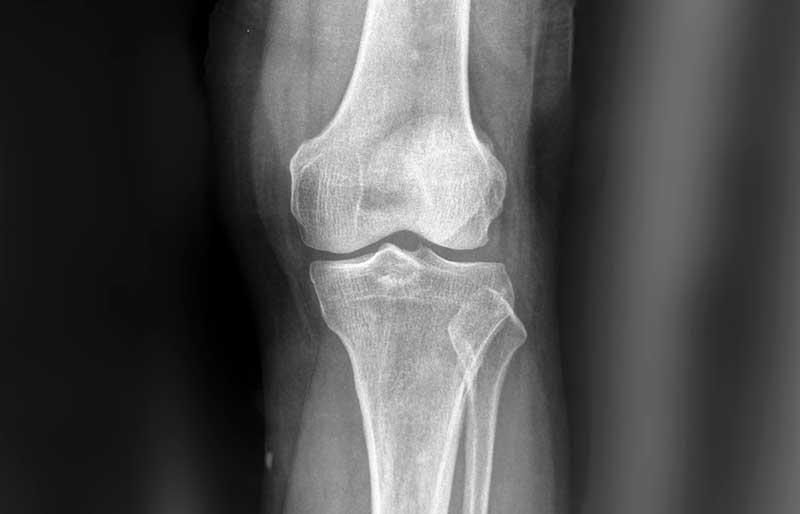

Osteoartritis (penipisan tulang rawan sendi) adalah suatu penyakit di mana tulang rawan mengalami kerusakan, penipisan dan akhirnya hilang sama sekali. Tulang rawan berfungsi melapisi ujung tulang pembentuk sendi agar tulang tidak saling bergesekan secara langsung, sehingga sendi dapat bergerak tanpa ham- batan dan rasa sakit. Osteoartritis adalah penyebab utama nyeri sendi, khususnya lutut dan panggul, pada orang berusia di atas 45 tahun. Osteoartritis sama sekali berbeda dengan osteoporosis (keropos tulang).

Osteoartritis disebabkan oleh kerusakan dan penipisan lapisan tulang rawan sendi. Penyebab kerusakan dan penipisan lapisan tulang rawan sendi pada osteoartritis adalah proses penuaan. Oleh karena itu, sebagian besar manusia akan mengalami penipisan tulang rawan dengan derajad yang berbeda-beda.